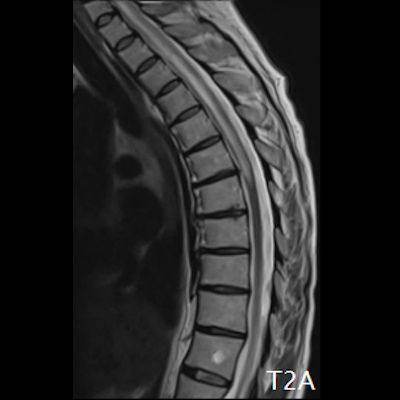

- (A) Torakal MRG’de sagital görüntülerde üst-orta torakal düzeyde T2A hiperintens (oklar), T1A izo-hipointens (ok) uzun segment ekspansil sinyal değişikliği izlenmekte olup sagital postkontrast T1A’da kontrast tutulumu mevcuttur (oklar). Bulgular longitudinal ekstensif transvers miyelit (LETM) ile uyumludur.

- Transvers miyelit sıklıkla santral gri cevheri etkileyen ve üç veya daha fazla vertebral gövde uzunluğunu etkilemektedir (LETM).

- Transvers kesitlerde, santral kordu tutma eğilimindedir.

- Omurilik atrofisi ve ekspansiyon/ödem MS’e göre daha fazla görülür.